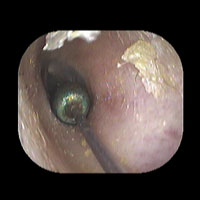

左急性中耳炎(重症)

鼓膜がやや赤くなって腫れています。鼓膜の奥に膿が透けて見えています。抗生剤の内服で鼓膜切開を行わずに22日目で治りました。

初診日